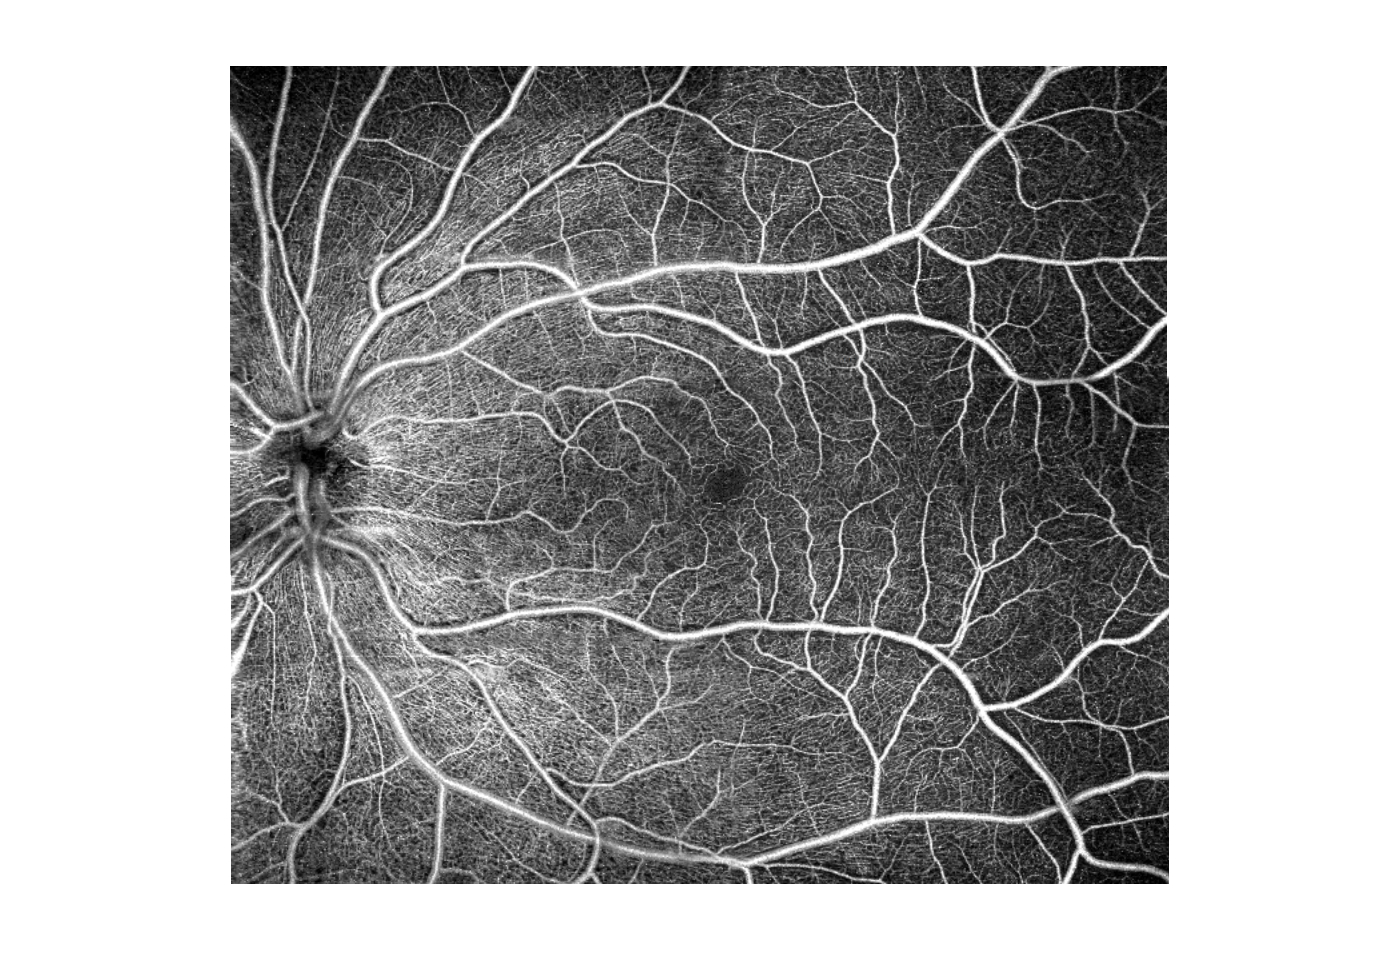

Imaging-Processing zur Darstellung von Blutgefäßen aus OCT-Bildern. Es ermöglicht eine klare Visualisierung des mikrovaskulären Blutflusses mittels nicht-invasiver OCT-Angiographie. Die OCT-Angiographie ermöglicht die Visualisierung von perfundierten Gefäßen und Gefäßanomalien der Netzhaut ohne Kontrastmittel. Blutgefäße können in einer bestimmten Gefäßschicht beobachtet werden. Es ermöglicht dem Arzt die Beurteilung der Mikrozirkulation bei Augenerkrankungen mit mikrovaskulären Details.

- Retina: 3 x 3 mm, 5 x 5 mm, 6 x 6 mm, 7 x7 mm, 8 x 8 mm, 9 x 9 mm

- Superficial Plexus

- Deep: tiefer kapillarer Plexus

- Outer: avaskuläre Zone

- Choriocapilaries-Choroidal-Kapillare-Zone

- Choroid-Choroidale Gefäße